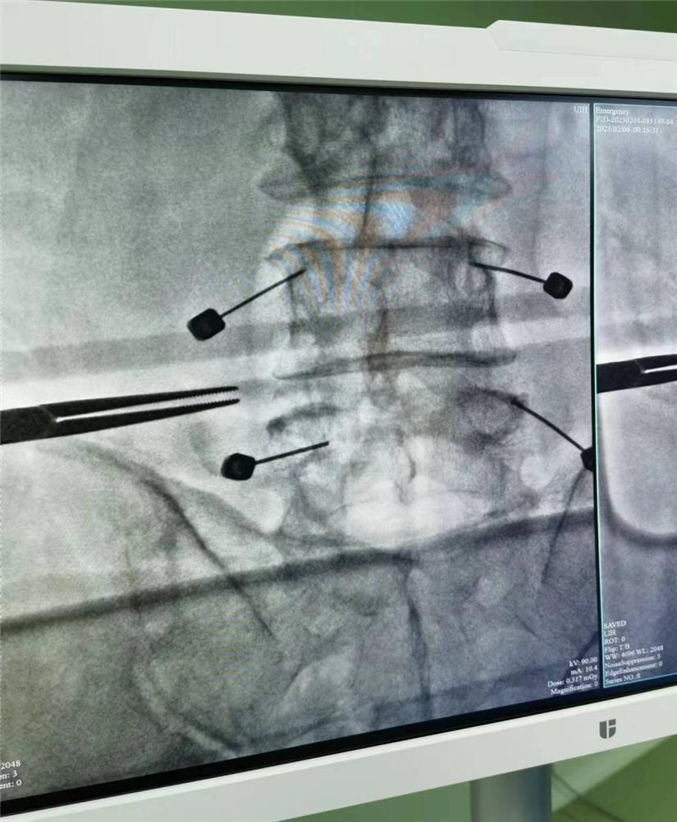

62岁的患者张先生,近2年来时常腰疼伴有左下肢疼痛,行放射线检查结果提示:腰4、5间盘突出,压迫硬膜囊,同时伴有脊柱不稳,行保守治疗效果不佳。患者就诊多家医院,最终选择我院骨科二病房住院治疗。经过和患者详细沟通及科室多次会诊后,骨科二病房团队最终为患者制定了腰4、5经皮椎弓根钉内固定、间盘镜下间盘摘除、椎间植骨融合内固定术的手术方案。术后患者腰疼及下肢的疼痛明显缓解,现已康复出院。

大多数腰椎间盘突出症患者选择保守治疗,但当保守治疗无效并影响生活质量时便可以考虑手术治疗。传统的腰椎间盘突出症需要行开放手术也就是传统的大切口,广泛剥离腰旁组织来完成,手术创伤大,手术效果不确切。近几年来我科已经自主完成了多例经皮椎弓根钉内固定术、间盘镜下单纯髓核摘除术,在此基础上,我们又进一步将两种微创手术相互融合、相互叠加,开展类似于MIS-TILF的术式即经皮椎弓根钉+间盘镜下间盘摘除植骨融合内固定术。该术以其微创切口,不用广泛剥离椎旁肌,创伤小恢复快等优势为广大腰间盘突出症患者带来了新的治疗选择。